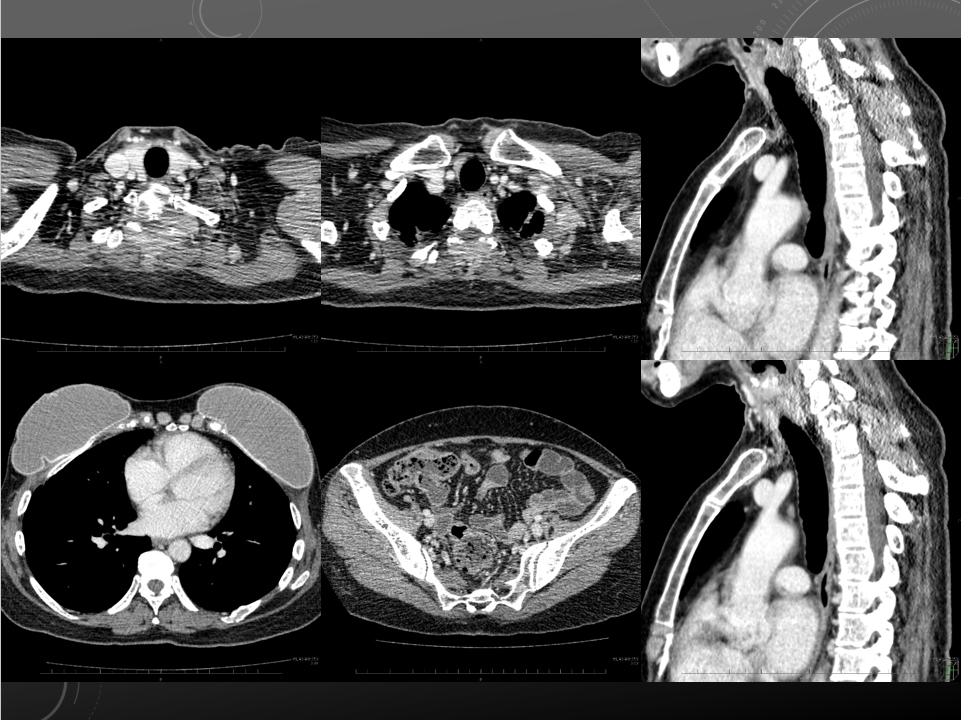

左背部の疼痛精査、転移のチェック

肺炎、胸膜炎チェック

Th1~3の棘突起周囲を中心に軟部組織あり骨転移疑われます。

左第8肋骨の骨皮質不連続性あり、骨転移の可能性があります。

以上は左背部痛の原因と考えられます。

多発リンパ節転移もやや増大。

肝転移も図のように新たな転移も出現。

肺野では不整形高吸収域散見されます。概ね変化ありません。

activeな肺炎像や胸膜炎を示唆する所見は指摘できません。

胸腹水認めません。

その他、スキャン内で新たに出現した active lesion はありません。

一つ前のCTからあったが指摘出来ず

前回2018年9月26日の CT と比較しています。

局所再発所見は見られませんが、左頸部から鎖骨下、左腋窩にかけて多数の腫大したリンパ節があり転移ですが、前回よりも図のように増大しています。

肺野に関しては前回左 S8 領域ですりガラス状の高吸収域が見られていましたが、今回は目立たなくなっています。上葉に散見される結節については概ね変化ありません。

その他、肺野内で今回新たに出現した active lesion は指摘できません。

肝転移も図のように増大しています。

その他、腹部で今回新たに出現した active lesion はありません。

骨破壊を伴うような骨転移の出現は認めません。